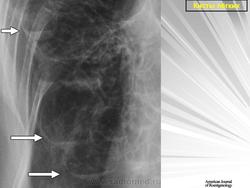

Воздушные кисты

Приложения:

1.vk_.slayd46.jpg